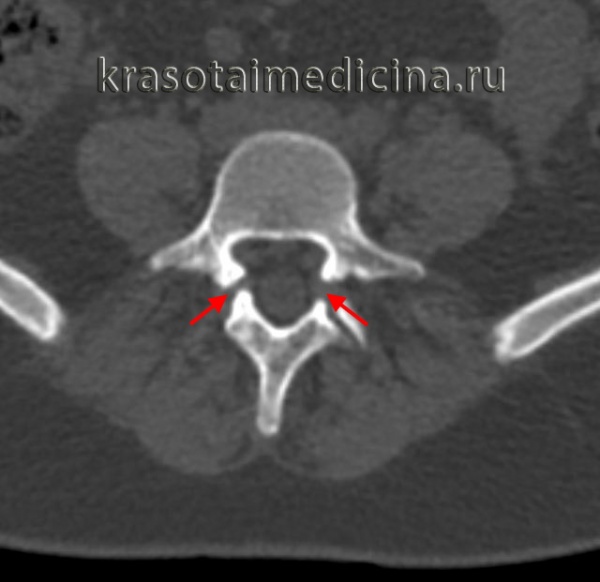

3. КТ при спондилолизе:

• Костная КТ:

о Симптом «незавершенного кольца» на аксиальных изображениях:

- Нарушение непрерывности кольца, образованного телом и дугой позвонка

о Зона дефекта может выглядеть как дугоотростчатый сустав:

- Признаки «добавочной фасетки»

- Горизонтальная или косая ориентация

- Неправильной формы или ровные кортикальные края

о Дефекты МЧ хорошо видны на косых реконструкциях

КТ пояснично-крестцового отдела позвоночника. Нарушение целостности задних отделов позвонка без существенного спондилолистеза.